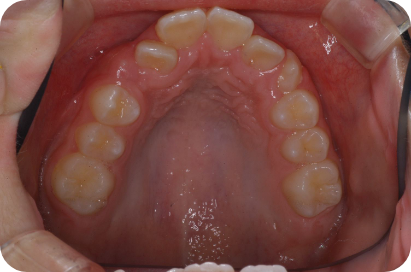

Tさん

Before

After

- 形態:狭いV型の上顎を丸くて広いU型に改善、歯ならび、咬み合わせの改善

- 機能:咀嚼嚥下トレーニング、口腔周囲筋トレーニング、姿勢改善